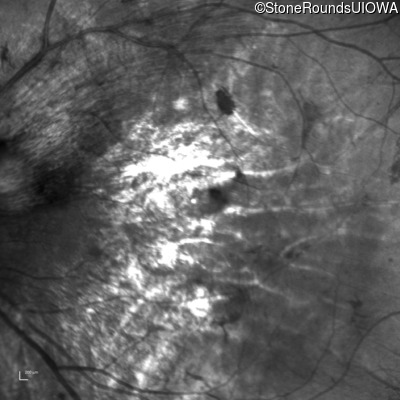

Infrared Fundus Photograph - Left - 5/160

Exemplar